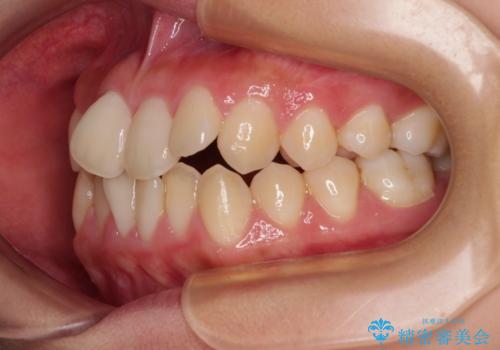

- 前歯のデコボコと唇の閉じにくさを気にして来院された患者様です。

単純に上下左右の第一小臼歯4本を抜歯して口元の突出感を改善することも考えられましたが、上顎骨よりも下顎骨の幅が広いため、より良い咬み合わせを達成することを目的として、急速拡大装置を用いて上顎骨を拡大することとしました。